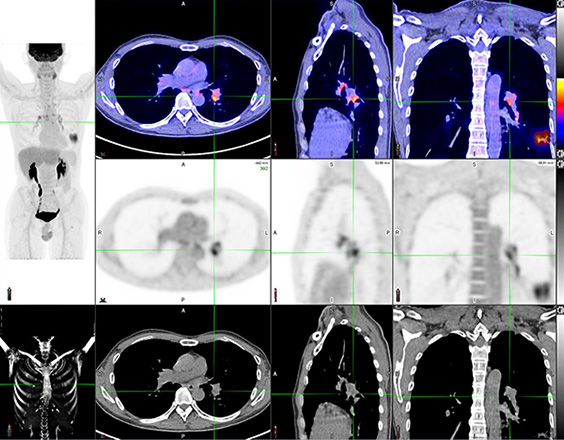

Positron Emission Tomography/Computed Tomography (PET/CT) is one of the most effective methods for cancer imaging and diagnosis. During the course of cancer development, metabolic changes always come earlier than structural or morphological changes in tissues and organs. Therefore PET/CT being a powerful camera capable of imaging our metabolic functions, it can facilitate early cancer detection and staging through the identification of the tumor biological characteristic.

PET tracers work as the biological imaging probe. Some of the commonly applied PET tracers include: PET radionuclide labelled deoxyglucose, acetate, DOTA-conjugated peptides, prostatic specific membrane antigen, etc. After injection, the tracer is absorbed based on organs’ structure as well as cell metabolism. The patient is then scanned with the PET/CT scanner to pick up any signals emitted from the tracer and hence the lesion location can be identified and uptake can be quantified. With this unique piece of medical information, we can locate lesions precisely and also help the assessment of treatment effectiveness.

PET/CT offers multiple parameters to quantify the cell activity which has a broad clinical application like cancer, cardiac, neurological diseases, etc. Apart from the most common “Standardized Uptake Value (SUV)”, the latest application involves mathematic calculation on the image data to retrieve even more unique dynamic parameters (such as “Patlak Analysis” for absolute metabolic rate, distribution volume of the pharmacology, theranostics and dose planning in radiotherapy). It creates unlimited possibilities in diagnosis and treatment planning.